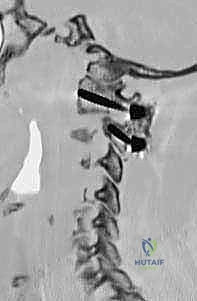

تُعرف التقنية الأكثر شيوعاً وفعالية اليوم باسم تقنية هارمز/جويل (Harms/Goel Technique)، والتي تتضمن وضع مسامير في الكتل المفصلية للفقرة C1 ومسامير في عنيقة أو جزء (Pars) الفقرة C2، ثم ربطها بقضبان معدنية. يتطلب هذا الإجراء مهارة جراحية فائقة، استخدام الميكروسكوب الجراحي، والتوجيه بالأشعة السينية داخل غرفة العمليات.

يتم تحديد نقطة الدخول على الكتلة المفصلية للفقرة C1. باستخدام مثقاب عالي السرعة (High-speed burr) ثم مثقاب يدوي دقيق، يتم عمل مسار للمسمار. يتم توجيه المسار بدقة ليكون موازياً للقوس الأمامي ومتجهاً قليلاً للداخل نحو مركز الفقرة لتجنب الشريان الفقري الذي يقع في الخارج. يتم إدخال مسمار من التيتانيوم (عادة بقطر 3.5 مم) في كل جانب.

الخطوة 5: إدخال المسامير في الفقرة الثانية (C2 Pedicle/Pars Screws)

بنفس الدقة، يتم تحديد نقطة الدخول في الفقرة C2. اعتماداً على التشريح الفردي للمريض (الذي تمت دراسته مسبقاً عبر الأشعة المقطعية)، يختار الدكتور هطيف إما مسار العنيقة (Pedicle) أو مسار الجزء البين مفصلي (Pars). يتم إدخال المسامير بزاوية محددة لضمان أقصى قوة تثبيت دون اختراق القناة الشوكية أو ثقبة الشريان الفقري.

الخطوة 6: تركيب القضبان واستعادة المحاذاة (Reduction)

بعد وضع المسامير الأربعة بنجاح، يتم تقييم وضعية الفقرات. إذا كانت C1 منزلقة للأمام، يتم استخدام أدوات خاصة لسحبها للخلف واستعادة المحاذاة الطبيعية مع C2 (عملية تُسمى Reduction). بمجرد تحقيق الوضعية المثالية، يتم قص قضيبين من التيتانيوم بالطول المناسب وتثبيتهما بقوة في رؤوس المسامير. هذا يخلق "سقالة" معدنية صلبة تمنع أي حركة بين الفقرتين.